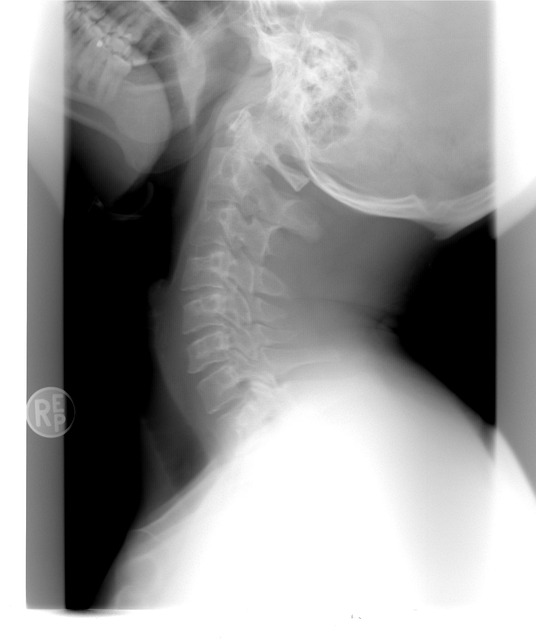

2. 잘못된 자세와 근육 불균형

- 장시간 앉아 있거나 구부정한 자세, 고개 숙임 습관 등은 특정 부위의 근육을 지속적으로 긴장시켜 통증을 유발한다

- 거북목, 라운드숄더, 골반 틀어짐 등이 대표적인 원인

| 허리 | 자세 불균형, 근력 약화, 디스크 초기 |